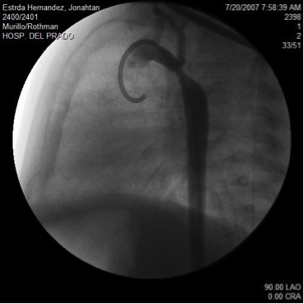

The catheter is moved through the heart with the aid of fluoroscopy (x-ray machine). This is usually performed to help in providing a diagnosis of heart problems.

X-ray dye can also be injected through the catheters giving pictures of structures in and around the heart.